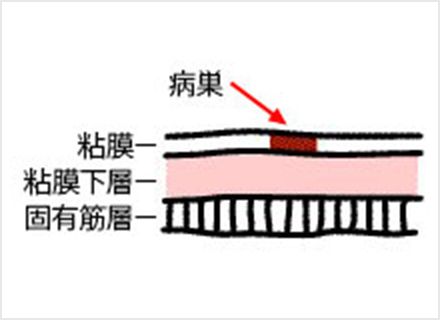

内視鏡治療の対象となる胃がんは、病変が一括で取れる部位と大きさであり、リンパ節転移の可能性がほとんどないほぼ粘膜内にとどまっていると診断された早期胃がんになります。

内視鏡的治療が外科手術に比べ優れた点は、入院期間が短い上に、おなかに傷がつかず、大きな併発症がなければ退院後の食生活、社会生活に支障がないことです。劣っている点は、切除した組織の状態によっては遺残病変の有無が確認困難な場合があり、将来再発する可能性があることや、切り取った病変の組織検査の結果、局所にがん細胞が残っている可能性がある場合や、がんがリンパ節に転移している可能性があると判断された場合は、さらに外科手術が必要になることです。

内視鏡を使った早期胃がんの治療法には、内視鏡的粘膜切除術(EMR)と内視鏡的粘膜下層剥離術(ESD)の2種類があります。

内視鏡的粘膜切除術:EMR(Endoscopic mucosal resection)

スネアと呼ばれる金属の輪を病変部に引っ掛け、高周波電流を流して病変を切り取ります。EMRは、治療が比較的短時間ですみますが、一度に切り取ることができる病変の大きさは、スネアの大きさ(約2cm)までと制限があります。